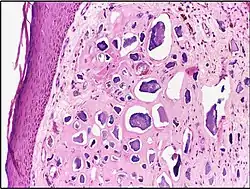

Micrograph of calcinosis cutis. The calcification is purple (bottom of image). H&E stain.

Calcinosis cutis is a type of calcinosis wherein calcium deposits form in the skin. A variety of factors can result in this condition. The most common source is dystrophic calcification, which occurs in soft tissue as a response to injury. In addition, calcinosis is seen in Limited Cutaneous Systemic Sclerosis, also known as CREST syndrome (the "C" in CREST). In dogs, calcinosis cutis is found in young, large breed dogs and is thought to occur after a traumatic injury.